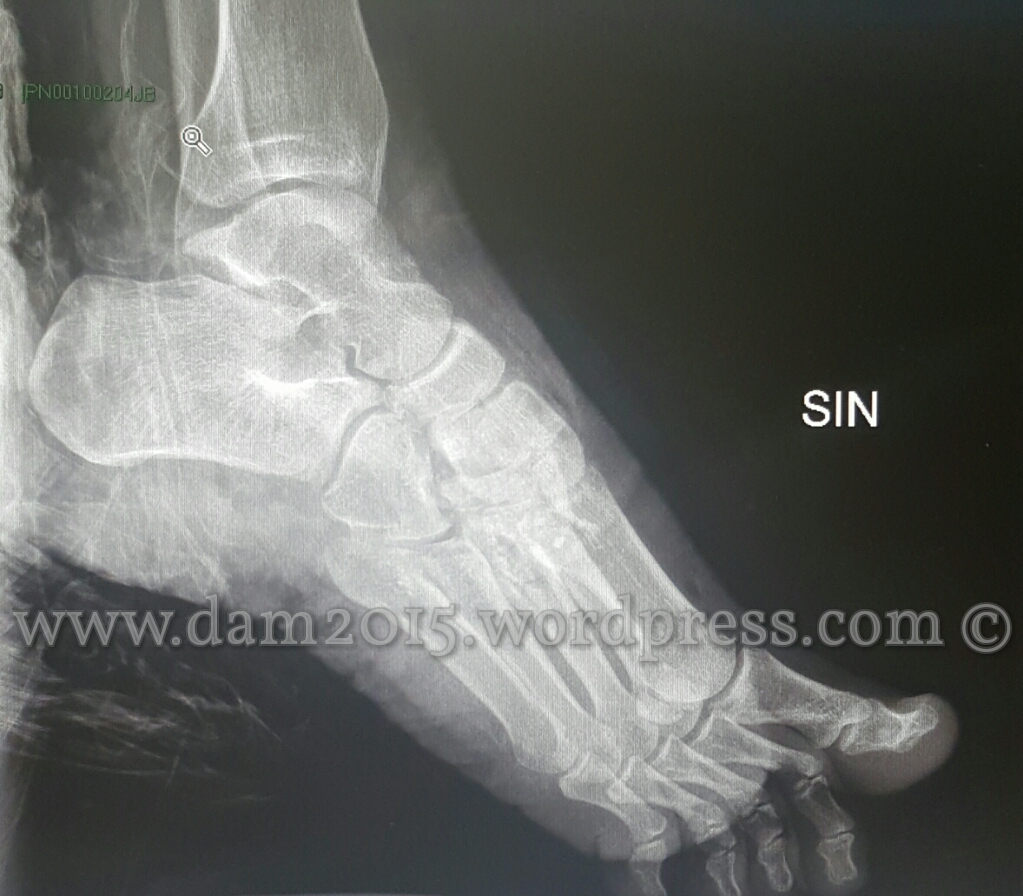

Investimento pedonale con conseguente trauma dell’arto inferiore di sinistra con frattura esposta ed esposizione tendinea.